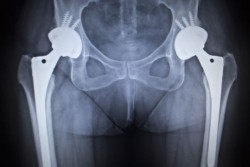

hip replacement lawsuitBiomet Orthopedics is facing a new metal hip replacement lawsuit from a California man alleging he suffered from serious hip replacement problems after undergoing surgery to implant a Biomet hip replacement device.

Metal-on-metal hip implants have been at the center of negative orthopedic patient experiences for the past several years, with new complaints filed with the FDA on a regular basis.

According to reports, the metal ball and metal socket in the joint of the hip implants interact, shedding metal ions into the patient’s blood stream.

This causes the formation of pseudotumors, infection, corrosion, device failure, and a number of other hip implant replacement problems. Initially all metal hip implants were thought to be more durable and longer lasting than the ceramic or plastic models, as well as being customizable for patients.